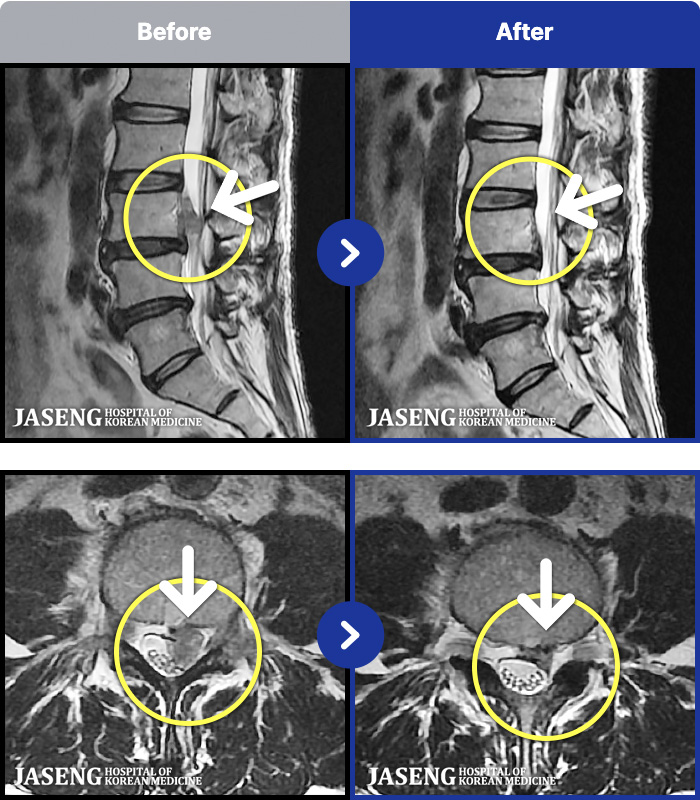

103 MRI ũ ʸ Ȯϼ.

ȯںп Ǹ ǿ ԿǾ, ο ġ ۿ Ƿ ġḦ Ͻñ ٶϴ.